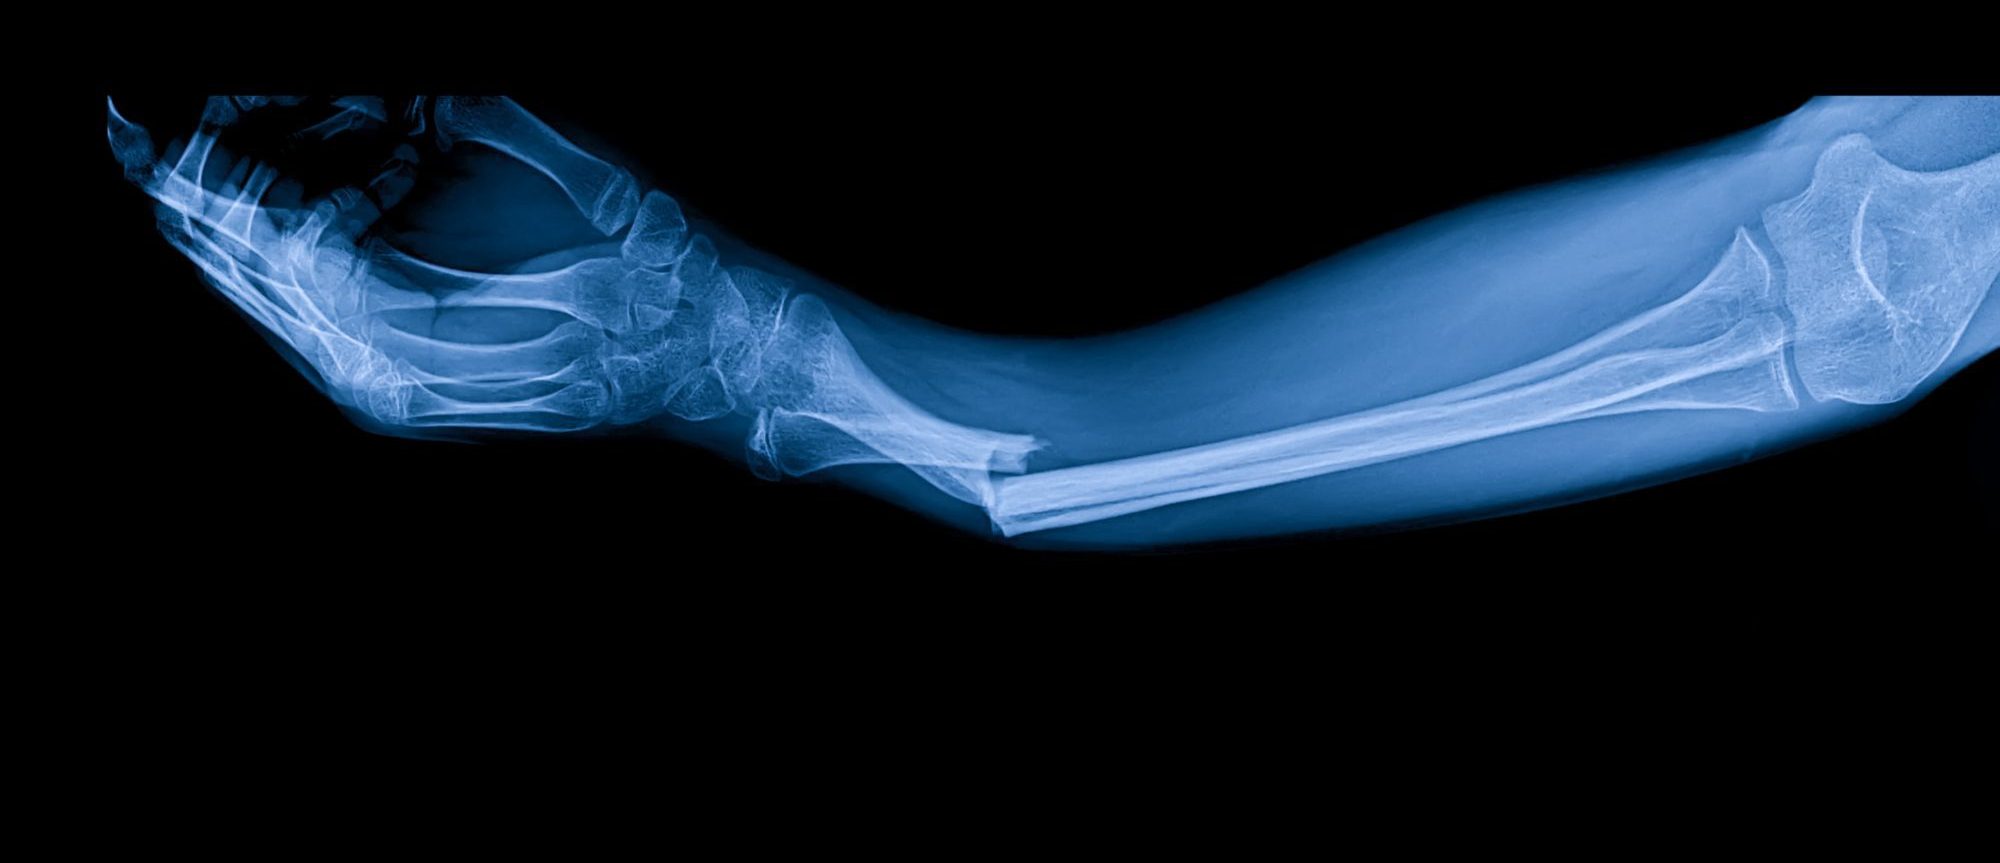

Not all broken bones are the same, and the type of fracture can affect your recovery and the compensation you may seek.

• Simple Fracture: The bone breaks cleanly, but the skin remains intact. While often less complex, these fractures still require significant medical care and can lead to complications.

• Compound Fracture: The broken bone pierces the skin, creating an open wound. This type of injury carries a high risk of infection and may lead to long-term complications, making treatment more expensive.

• Comminuted Fracture: The bone shatters into three or more pieces. These severe injuries often require complex surgery, such as the insertion of plates and screws. Recovery is typically long, and permanent disability is possible.

The severity of your fracture directly influences your medical costs, recovery time, and the level of compensation you might be entitled to.